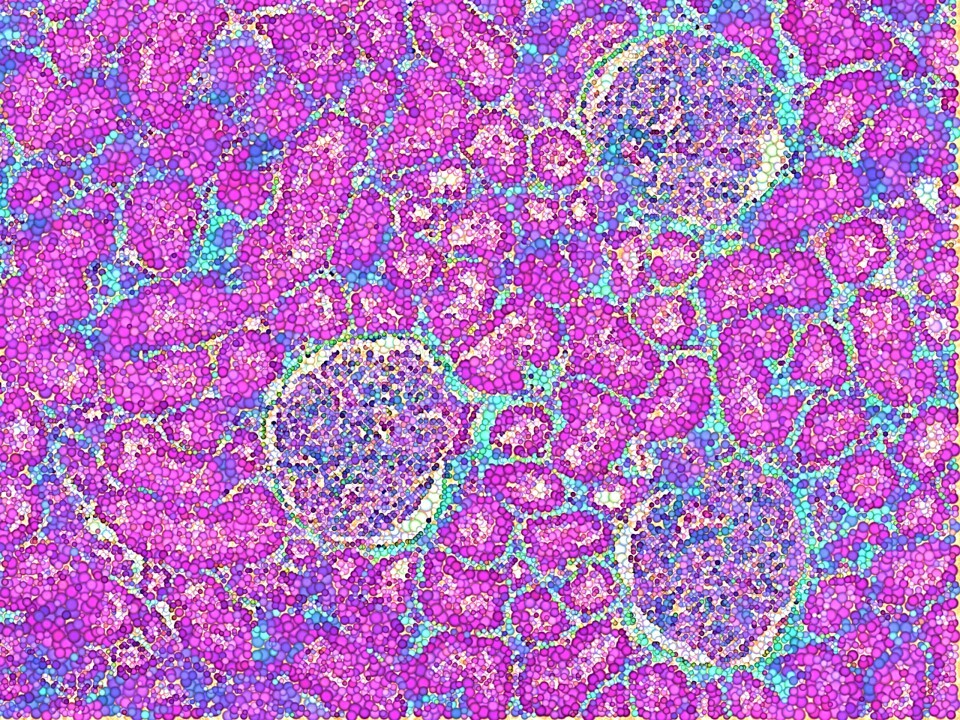

Header Image: an artistic rendition of a region of the renal cortex of stone-formers with glomeruli stained with Masson's Trichrome to highlight biomarkers of collagen, and tissue pathology. Image credit: Author's own.